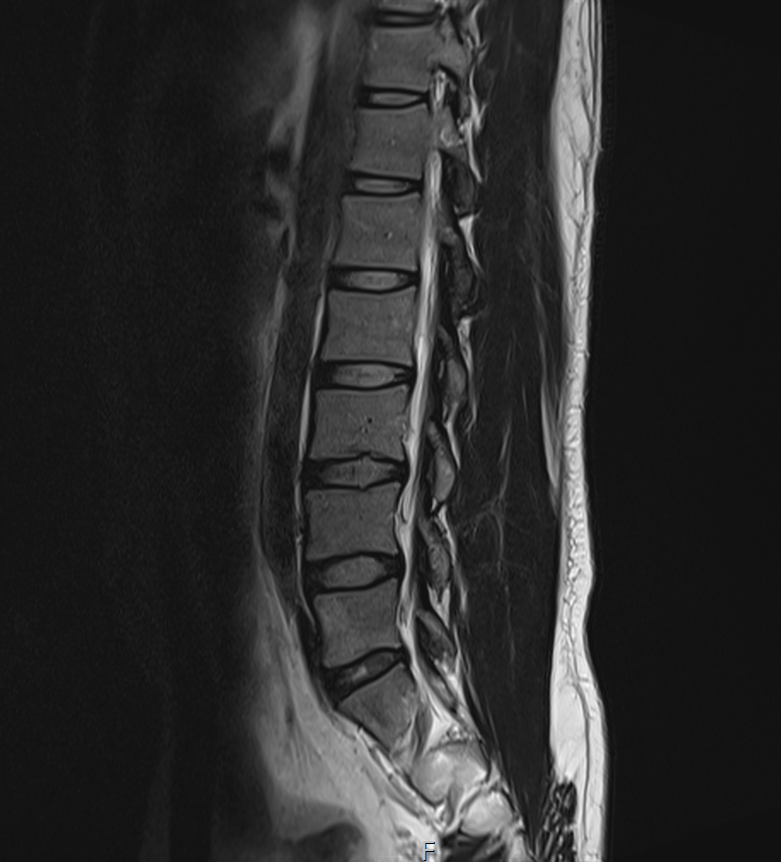

MRI 판독지 및 사진 해석 부탁드립니다.

1년전에 허리가 안좋아서 MRI를 찍었는데 저번주에 경미한 교통사고가 났습니다.

그 후 다리에 저림증상이 있기 시작했고 피가 안통하는 느낌이 들기 시작했습니다.

경미한 교통사고가 다리저림에 원인일 수 있을까요? MRI판독 부탁드립니다 ㅠㅠ

현재

• 2번 째 사진

1년 전 사진에 비해 허리디스크 상황이 악화된 것으로 생각됩니다. 다리저림은 이로 인한 증상으로 생각됩니다.

그러나, 말씀하신 내용과 검사결과만으로는 교통사고와의 연관성에 대해 단정지어 말하기는 어렵습니다. 증상이 점차 악화되어 발생한 것인지, 교통사고에 의해 갑자기 악화된 것인지에 대한 판단이 추가로 필요하겠습니다.